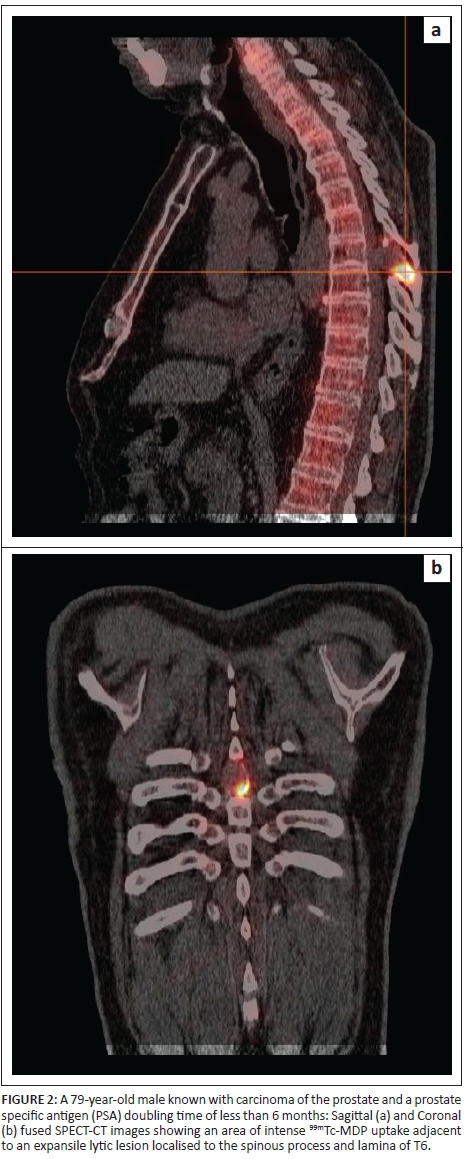

The addition of CT detected more lesions in a quarter of the patients while SPECT-CT markedly increased the interpreter's confidence with respect to lesion localisation and categorisation in comparison with SPECT and planar images (Figures 1 and 2). This agrees with the reports from other studies.2,4,5,6,7,14,15 In addition, some of these studies reported marked reduction of indeterminate lesions from a rate of between 48% and 72% using whole body planar scintigraphy with or without SPECT, to a rate between 0% and 15%.4,5,6 The current study showed a reduction in the indeterminate lesion rate among patients referred for 99mTc-MDP bone scintigraphy from 21.3% on planar alone to 11.2% and 3.6% following the addition of SPECT and SPECT-CT, respectively. While the proportion of SPECT-CT indeterminate lesions in this study is similar to that found in the study reported by Palmedo et al.,15 the lower rate found on the planar images in the current study may be due to the criteria used when referring patients for scintigraphy.